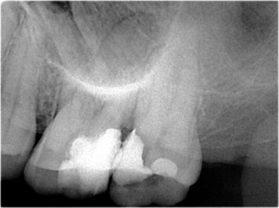

(a) Pre-operative radiograph of tooth #16, (b) Occlusal view of the ...

A) Consecutive slices showing an II pattern in a filled MB2 canal. B ...